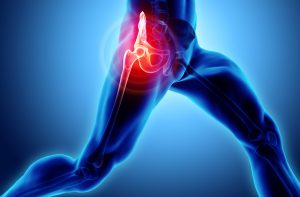

درد مفصل ران یک بیماری شایع است که می تواند در اثر عوامل مختلفی از جمله آسیب، استفاده بیش از حد و شرایط تخریبی مانند آرتروز ایجاد شود.

مفصل ران یکی از بزرگترین مفاصل بدن است و وظیفه تحمل وزن بالای بدن را بر عهده دارد و امکان انجام حرکات مختلفی مانند راه رفتن، دویدن و پریدن را به عهده دارد.

درد در مفصل ران می تواند از خفیف تا شدید متغیر باشد و می تواند در کشاله ران، ران، باسن یا حتی زانو احساس شود. همچنین می تواند با سفتی، تورم و مشکل در حرکت مفصل همراه باشد.